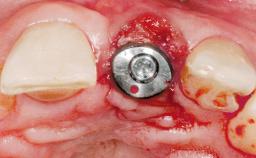

| # of Implants | 1 |

| Type of Implants | Two-Piece |

| Bone Volume | Deficient horizontally, requiring prior grafting |